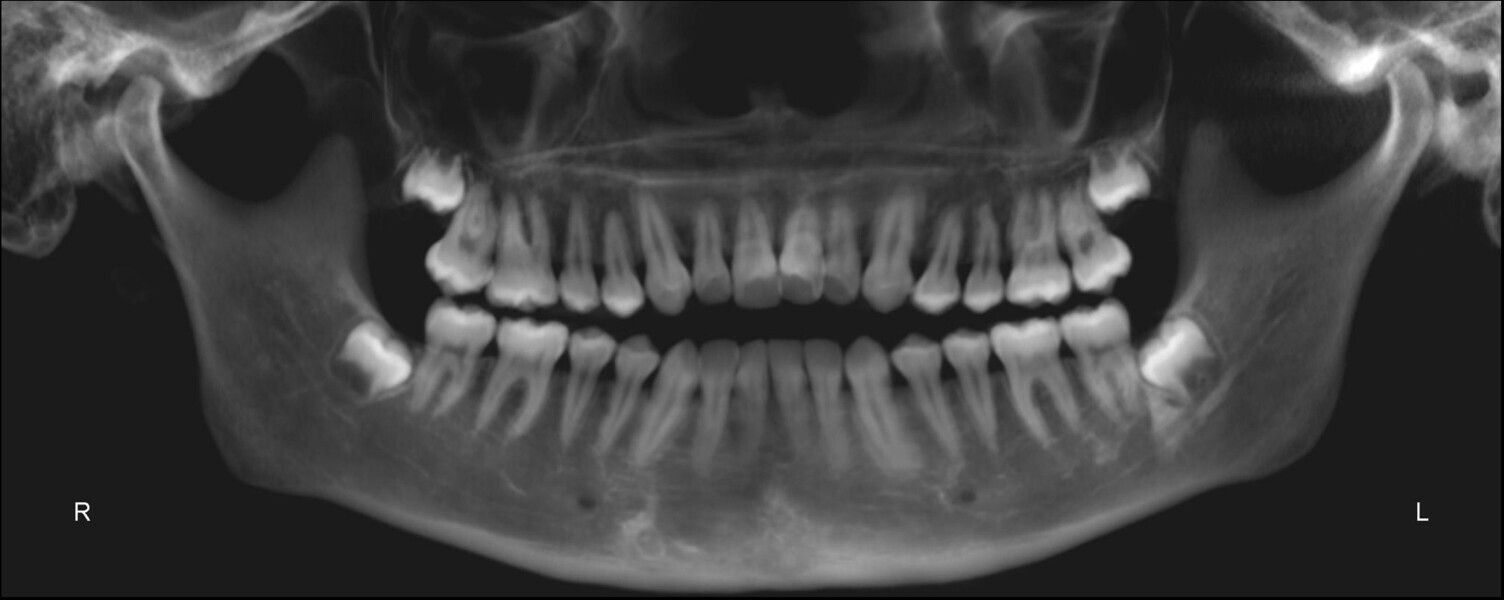

The panoramic radiograph showed prior extraction of all third molars, localised root resorption of several teeth, generally good periodontal health and an atypical condylar morphology, suggestive of temporomandibular joint (TMJ) remodelling or degenerative changes (Fig. 19). The cephalometric radiograph and tracing revealed a mesobrachyfacial skeletal pattern and a tendency towards a Class II skeletal pattern (Fig. 20).

The post-treatment panoramic radiograph showed good root parallelism and no worsening of the pre-existing root resorption or periodontal condition (Fig. 32). The final cephalometric radiograph and tracing showed that, although the patient retained a Class II skeletal pattern, the values had improved owing to mandibular auto-rotation (ANB from 6.9° after splint therapy to 4.4° at the end of treatment). This auto-rotation had also improved the vertical measurements between the end of splint therapy and the end of treatment: maxillary inclination (SN–OP) had decreased from 18.6° to 16.2°, Ricketts’ facial axis from 92.7° to 91.4° and Jarabak’s sum of angles from 392.0° to 387.6° (Fig. 33).